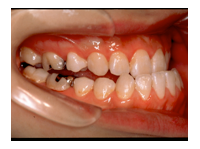

1) 主訴 下あごが出ている、前歯で咬むことができない、しゃべりにくい

2) 診断名 顎変形症(下顎近心変位)

3) 初診時年齢 22歳

5) 抜歯 新規抜歯はなし(ただし上顎左右の第一小臼歯は初診時には既に抜歯されていた)

6) 治療期間 開始時から装置装着まで3か月、術前矯正期間5か月、術前矯正期間3か月、保定期間3年

合計3年11か月